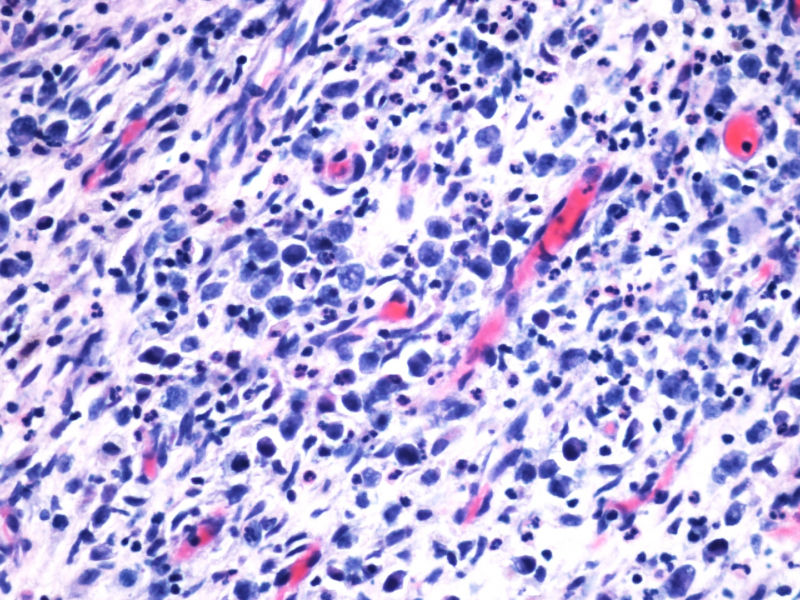

本例患者未查见淋巴结肿大,无肝脾肿大。其余标记物:大细胞显示CD2,CD3,CD4,CD8,CD5,EMA,TIA-1,GranB, oct, Bob1, EBER均阴性。

阳性的有CD30,CD15,CD43,ALK,perforin。

本例是大细胞病变;本例出现了“裸”免疫表型,这可在ALCL中出现;本例perforin阳性,支持是细胞毒性的大细胞淋巴瘤;大细胞同时表达CD30/CD15/ALK/细胞毒标志物,据目前文献报道,只有ALCL能解释;EBER阴性;临床影像学提示为溶骨性病变。。。

本例全B,全T缺失,使诊断很困难,淋巴瘤范围内一般考虑①HL;②浆细胞分化的肿瘤如浆细胞骨髓瘤或浆母细胞瘤;③ALCL. 以下为鉴别:

1.关于CD15:可见于HL,偶尔(WHO: rarely)见于ALCL,甚至可意外地或异常地(WHO: exceptionally)见于外周T,非特指.

2.关于PAX5:应该是HL和ALCL鉴别非常好的标记。WHO: The B-cell nature of HRS cell is further demonstrable in approximately 95% of cases by their expression of the B-cell specific activator protein PAX5. 本例PAX5阴性,重点就只有放在ALCL上了。

3.关于CD43: 对比CD43和CD3的结果,并不能否认ALCL,甚至还提供了一个线索就是CD3- 是由于肿瘤细胞“改头换面”缺失表达造成的,如果追加CD2,4,5等可能就会使肿瘤“原形毕露”了。

最后,ALK+可证实以上的推断。